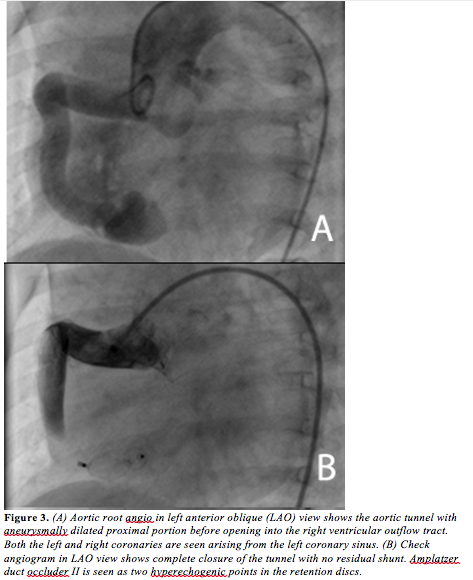

Cardiac catheterization was performed to confirm the diagnosis and to attempt transcatheter closure of the tunnel. Hemodynamic data showed Qp:Qs to be 3:1, with pulmonary artery pressures of 33/17 mm Hg (mean, 22 mm Hg). Aortic pressure was 100/20 mm Hg (mean, 47 mm Hg). Ascending aortogram done in left anterior oblique (LAO) view showed a dilated tortuous tract arising from the right side of the aortic root and draining into the right ventricular outflow tract (RVOT) with an aneurysmally dilated proximal portion (measuring 12 mm) with a narrow opening measuring 6 mm at the RV end (Figure 3A). A Terumo 0.018˝ wire was advanced into the fistulous tract from the aortic end through 4 Fr Cobra catheter into the RV and then into the pulmonary artery. A 4 Fr Cobra catheter was advanced over the wire. The tip of the wire was snared using a 15 mm Goose-neck snare advanced into the left pulmonary artery through the right femoral vein. The standard arteriovenous (AV) loop was made. Over this wire, a 7 Fr Cook shuttle delivery sheath was advanced into the fistula from the RV end with great difficulty. A futile attempt was made to introduce a 10 x 8 Amplatzer duct occluder (ADO). The check angiogram showed that the device was not in the tunnel. As there was an acute bend at the RV end of the tunnel, the large delivery sheath with the bulky ADO was not entering the tunnel. Hence, we decided to close the tunnel with the ADO II, which can be introduced from the aortic end without an AV loop as it has low profile.

The tunnel was recrossed from the aortic end with a 0.018˝ Terumo wire; over that, a 5 Fr Terumo catheter was introduced into the pulmonary artery and then exchanged with a 0.035˝ J-tip regular wire. A 5 Fr Cook shuttle sheath was advanced over the wire. A 6 x 6 ADO II device was loaded and advanced easily into the delivery sheath. The distal disc of the device was released in the pulmonary artery and the whole system was pulled to the opening of the tunnel in the RVOT. The position of the distal retention disc was checked both by TTE and angiography. Then, the rest of the device was deployed in the aneurysmally dilated portion of the tunnel. The device was released after the check angiogram showed good position of the device with no residual shunt (Figure 3B). After the procedure, on clinical examination, pulse was 100/min with normal volume, blood pressure was 100/80 mm Hg, and no murmur was heard on auscultation. The TTE with color Doppler in the subcostal view showed the device in situ with no residual shunt (Figure 4). The infant had an uneventful postprocedure stay in the hospital and is normal on follow-up after 9 months. The ECG remained normal.

The ADO II is made up of nitinol, a shape memory alloy of nickel and titanium. Each occluder is made up of a multilayered, flexible, nitinol wire mesh shaped into a cylindrical waist with retention discs on either end to secure it in position. Fabric-free technology (no polyester fabric), which allows for low-profile devices and delivery systems, creates superior deliverability and expanded procedural options. The advantage of the ADO II is that it has a very low profile and can be easily delivered through a 4 or 5 Fr sheath in infants. Since it has a retention disc on either side, it can be delivered from either end, which is especially useful in infants, and easy to track through tortuous tunnel with an acute bend as in our case. Since the narrow RV end measured 6 mm, we chose a 6 x 6 ADO II, so the mid-portion of the device snuggly fit the RV end and the 12 mm retention disc was perfect for the 12 mm aneurysmally dilated portion of the tunnel. Although the anatomy of the tunnel was not suitable for transcatheter closure from the venous end with a regular duct occluder, which is bulky, we accomplished successful device closure from the aortic end with the low-profile ADO II. To the best of our knowledge, this is the first and only case report of ARVT with biventricular apical non-compaction to be successfully closed using the new ADO II device in an infant.